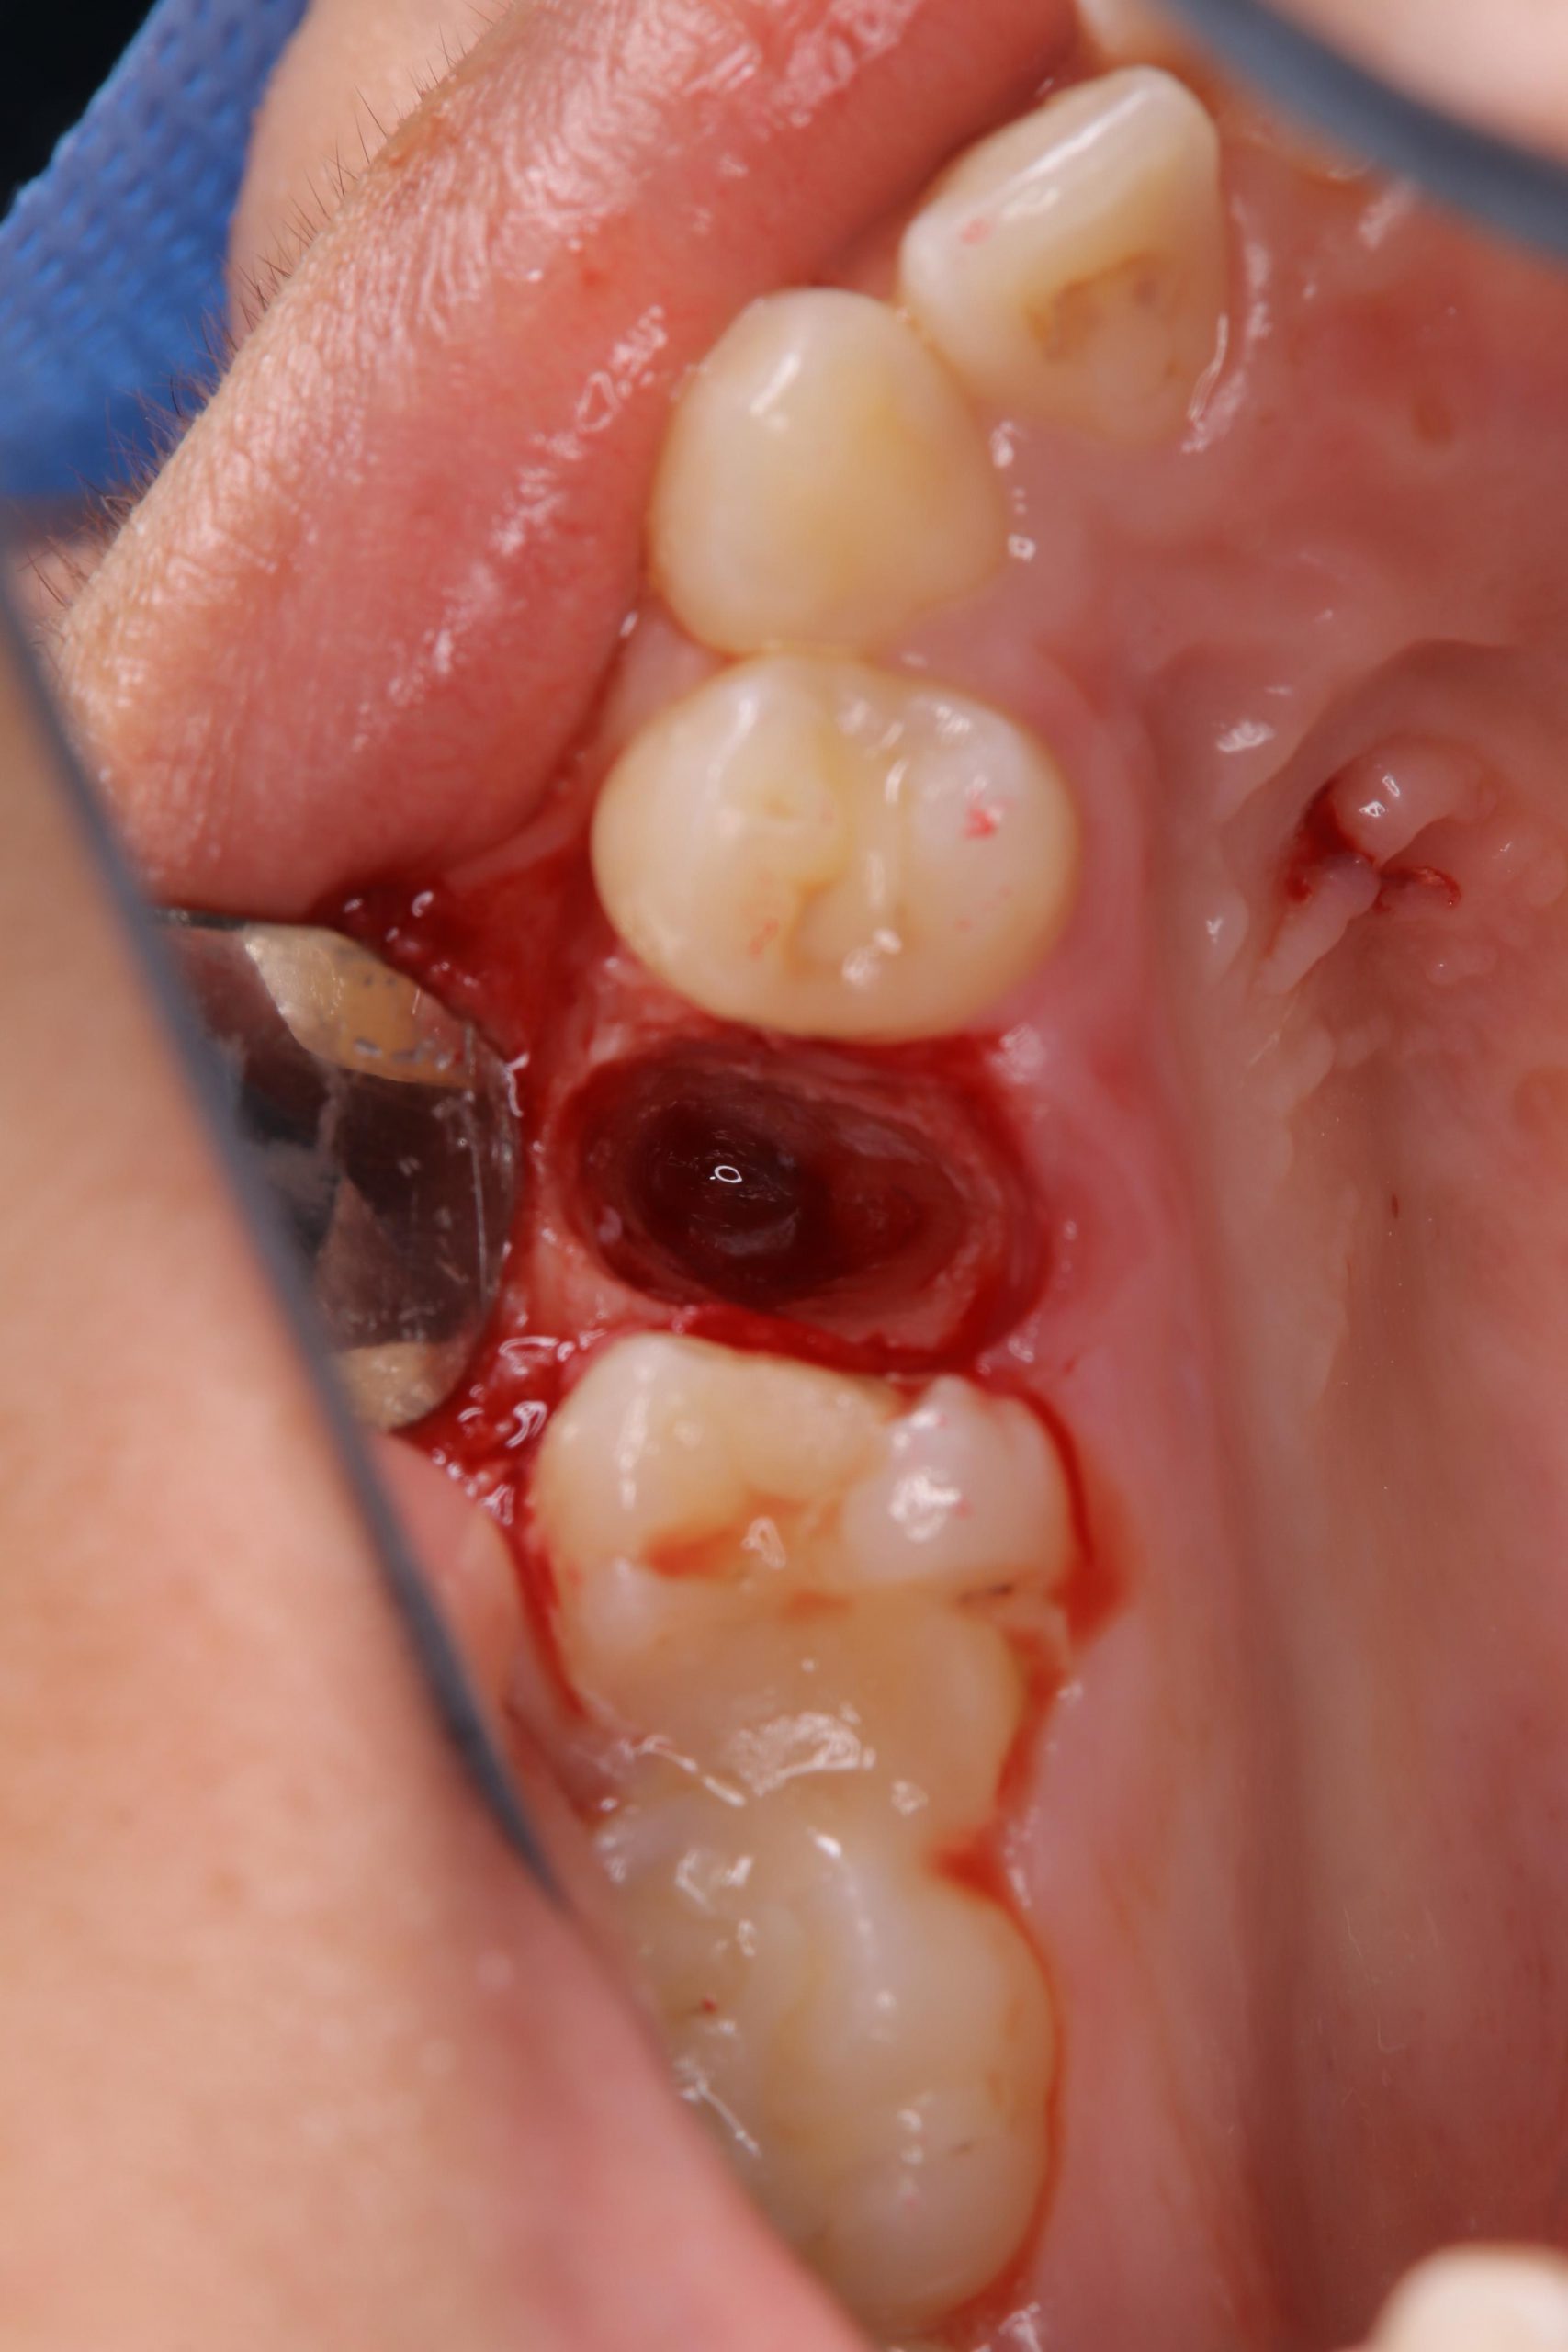

右上の第2小臼歯を抜歯し、ドナー歯である左上の過剰歯がソケットに収まるように骨の形態を調整し、

歯根膜の損傷に気を付けながら抜歯した過剰歯を

下の写真のように抜歯したソケットに移植しました。

レントゲン写真は移植直後のものです。